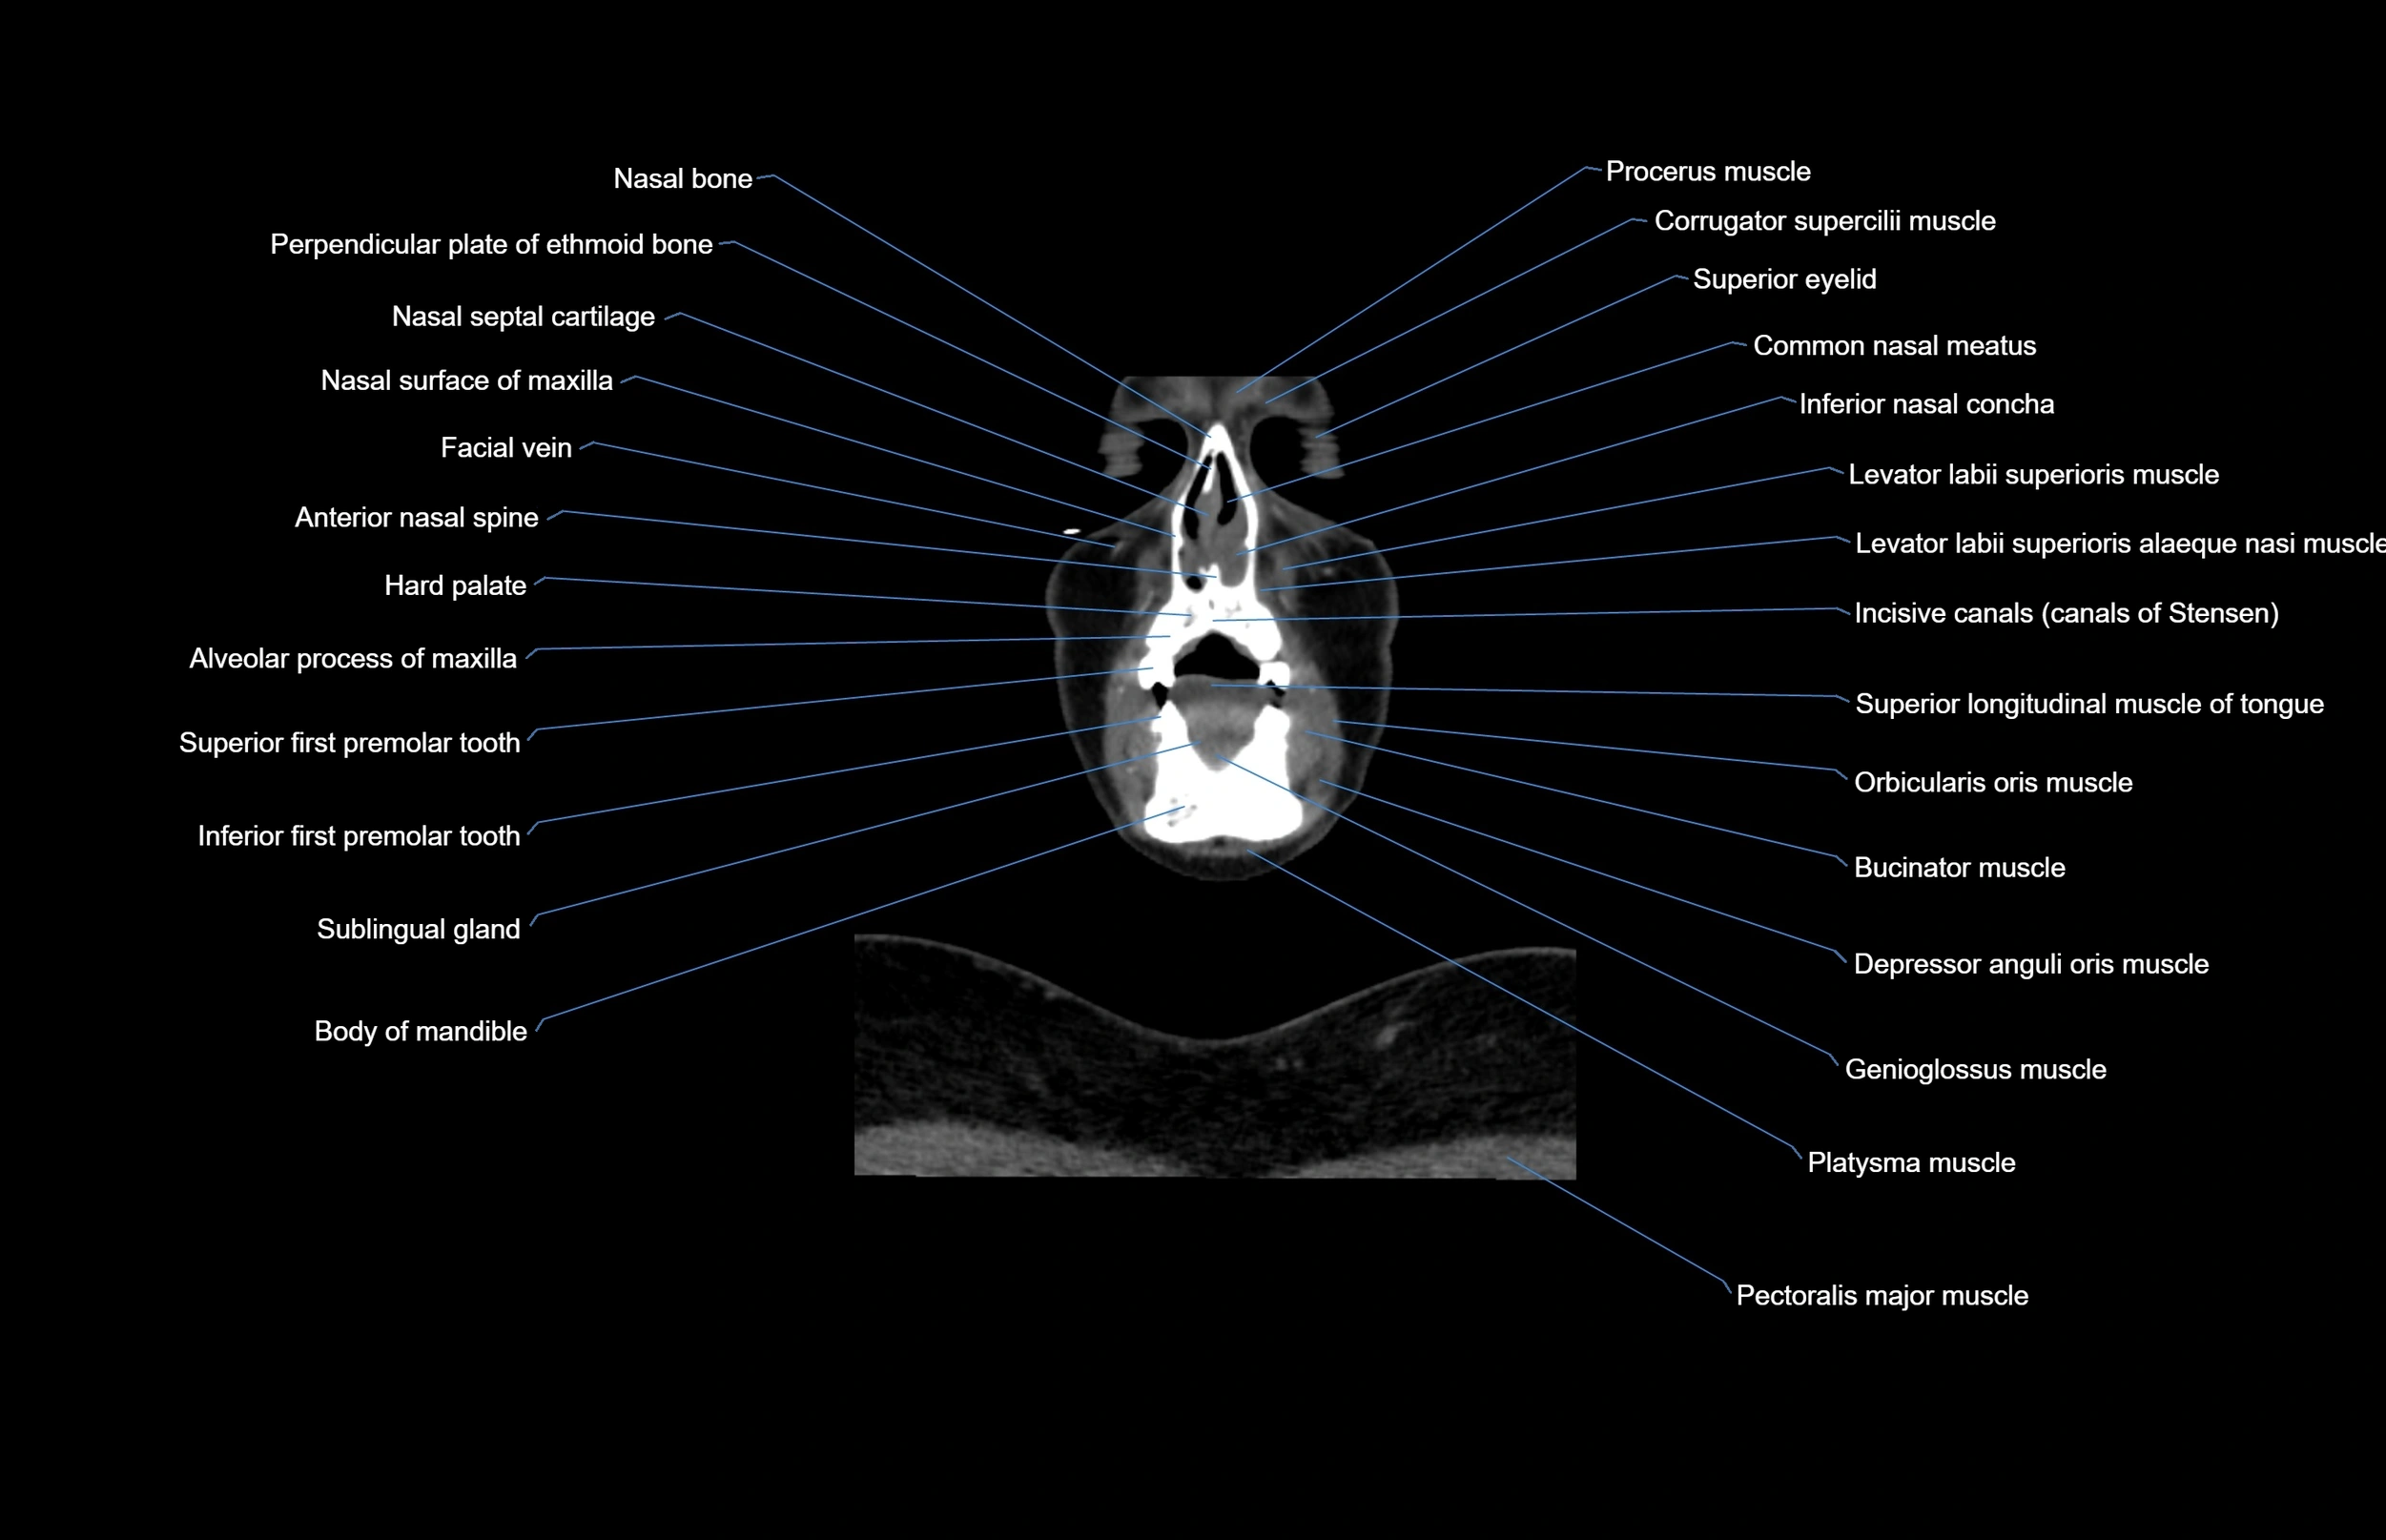

- Alveolar process of maxilla

- Common nasal meatus

- Hard palate

- Inferior first premolar tooth

- Inferior nasal concha

- Levator labii superioris alaeque nasi muscle

- Levator labii superioris muscle

- Nasal spine of frontal bone

- Orbicularis oris muscle

- Pectoralis major muscle

- Platysma muscle

- Sublingual gland

- Superior eyelid

- Superior longitudinal lingual muscle

- Superior longitudinal muscle of tongue